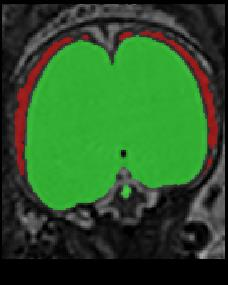

Limiting failures of machine learning systems is of paramount importance for safety-critical applications. In order to improve the robustness of machine learning systems, Distributionally Robust Optimization (DRO) has been proposed as a generalization of Empirical Risk Minimization (ERM). However, its use in deep learning has been severely restricted due to the relative inefficiency of the optimizers available for DRO in comparison to the wide-spread variants of Stochastic Gradient Descent (SGD) optimizers for ERM. We propose SGD with hardness weighted sampling, a principled and efficient optimization method for DRO in machine learning that is particularly suited in the context of deep learning. Similar to a hard example mining strategy in practice, the proposed algorithm is straightforward to implement and computationally as efficient as SGD-based optimizers used for deep learning, requiring minimal overhead computation. In contrast to typical ad hoc hard mining approaches, we prove the convergence of our DRO algorithm for over-parameterized deep learning networks with ReLU activation and a finite number of layers and parameters. Our experiments on fetal brain 3D MRI segmentation and brain tumor segmentation in MRI demonstrate the feasibility and the usefulness of our approach. Using our hardness weighted sampling for training a state-of-the-art deep learning pipeline leads to improved robustness to anatomical variabilities in automatic fetal brain 3D MRI segmentation using deep learning and to improved robustness to the image protocol variations in brain tumor segmentation. Our code is available at https://github.com/LucasFidon/HardnessWeightedSampler.